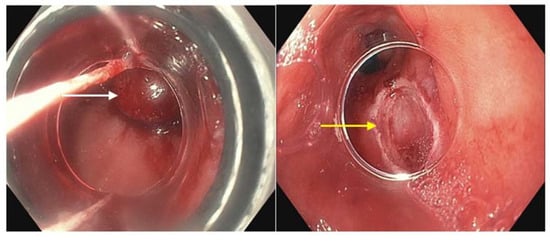

Virtual chromoendoscopy uses technology built directly into the endoscope. The most widely used system is the Olympus narrow band imaging (NBI) (Figure 1) which applies a red–green–blue light filter to maximally highlight the surface mucosa and vascular pattern of the tissue being examined [46]. This narrower spectrum of 400–540 nm (compared to 400–700 nm white light) is matched to the absorption of hemoglobin, causing tissues such as blood vessels and blood to appear darker compared to the surrounding mucosa. Other widely used systems include the Fujinon Intelligent Color Enhancement (FICE) and the Pentax iScan which capture white light images and digitally process them to enhance the surface mucosa and vascular pattern [47]. A meta-analysis of nine studies showed a pooled sensitivity and specificity of greater than 94% each of detecting BE with NBI [48]. A separate study indicated an overall reduction in the number of biopsies while still detecting high-grade dysplasia (HGD) and early adenocarcinoma when white-light and NBI endoscopy were compared [49]. Virtual chromoendoscopy adds no cost, additional time or risk to the patient while providing a useful adjunct during routine endoscopy.

Figure 1.

Narrow band imaging applied to a segment of Barrett’s esophagus (white arrow).